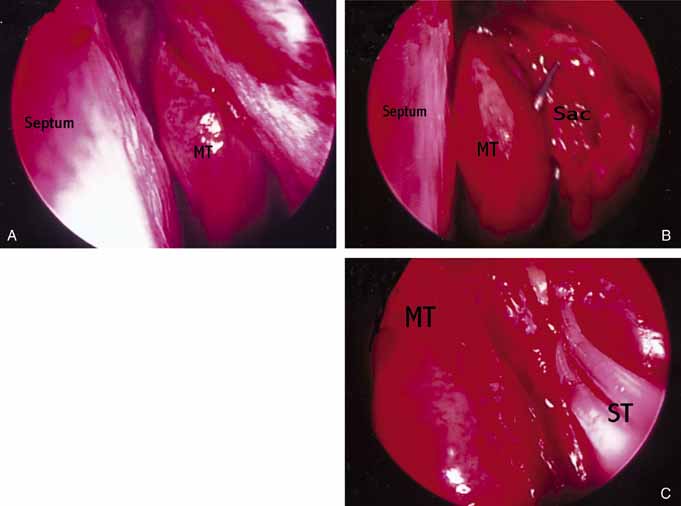

stented with bicanalicular Silastic stents and secured in place (Fig 47A, 47B, and 47C). This technique is efficient with minimal morbidity and no external

scar. However, because the lacrimal sac is not sewn to the nasal mucosa, the

ultimate size of the fistula reduces to that of the Silastic

tubing diameter. Some individuals have tried treating the fistula site

with topical mitomycin C to prevent the fistula opening from shrinking

with varied results. Overall, in experienced hands the endoscopic

approaches are efficient and effective with success rates well in the 90% range

similar to external DCR.  Fig. 47 Left endoscopic dacryocystorhinostomy (DCR). A. Endoscopic view of nasal cavity anterior to middle turbinate (MT). B. Lacrimal sac opened with Bowman probe in common canaliculus. C. Silastic stents (ST) in palce at end of operation. Fig. 47 Left endoscopic dacryocystorhinostomy (DCR). A. Endoscopic view of nasal cavity anterior to middle turbinate (MT). B. Lacrimal sac opened with Bowman probe in common canaliculus. C. Silastic stents (ST) in palce at end of operation.